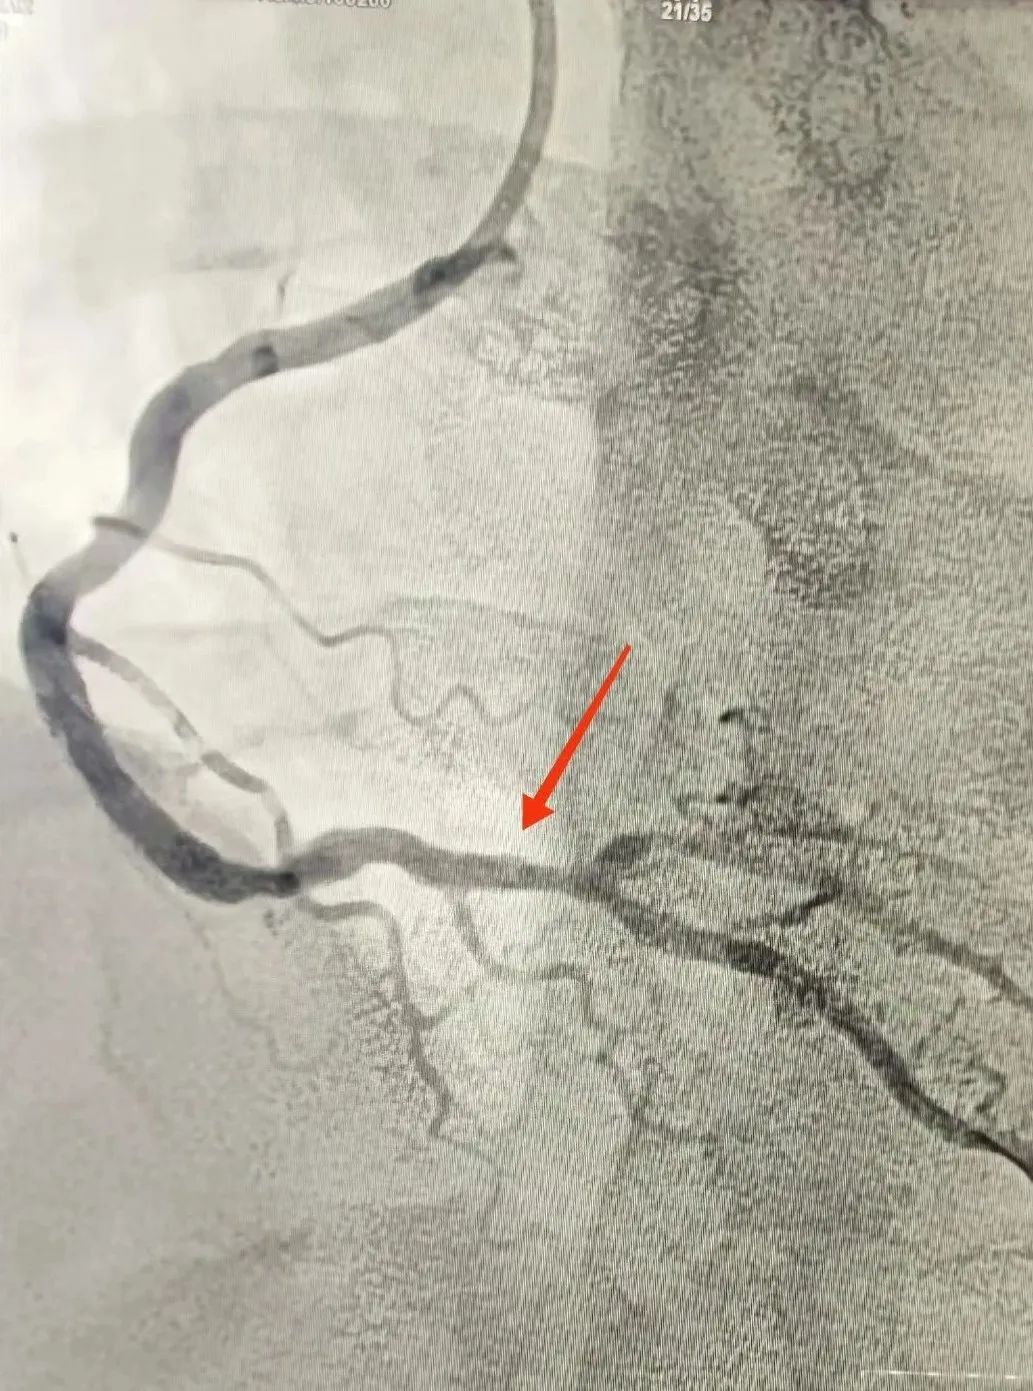

120救護車(che)到(dao)達蘇州九龍醫(yī)院後(hou),龍先(xian)生(sheng)直接被送到(dao)急診搶救室。醫(yī)護人(ren)員(yuan)立即對其完善(shan)相關檢(jian)查。心電(dian)圖提示:窦性心律,1度房室傳(chuan)導(dao)阻滞,II、III、AVF導(dao)聯(lian)ST段擡高(gao);考慮“急性心肌梗死”。情況十分(fēn)緊急,心血筦(guan)內(nei)科(ke)劉廣(guang)安(an)副主(zhu)任醫(yī)師團(tuán)隊(duì)來到(dao)急診搶救室會診,立即啓動(dòng)胸痛中(zhong)心綠色生(sheng)命通(tong)道,直達導(dao)筦(guan)室進(jin)行心髒血運重(zhong)建(jian)!急診“冠狀動(dòng)脈造(zao)影CAG術(shù)”提示:RCA遠(yuǎn)段完全閉塞,血流TIMI 0級;LAD狹窄30%,LCX遠(yuǎn)段狹窄40%。鑒于(yu)患者年(nian)紀輕且病情急,專(zhuan)傢(jia)團(tuán)隊(duì)決定爲(wei)其采用(yong)藥物(wù)球囊PTCA治療。藥物(wù)球囊手術(shù)通(tong)過(guo)向病變血筦(guan)部(bu)位輸(shu)送藥物(wù),達到(dao)擴張血筦(guan)、抑製(zhi)血筦(guan)再狹窄的(de)效果。這種手術(shù)方(fang)式(shi)創傷小(xiǎo)、恢複快,适郃(he)年(nian)輕患者咊(he)需要避免長(zhang)期支架植入的(de)患者。

術(shù)前(qian)

術(shù)後(hou)